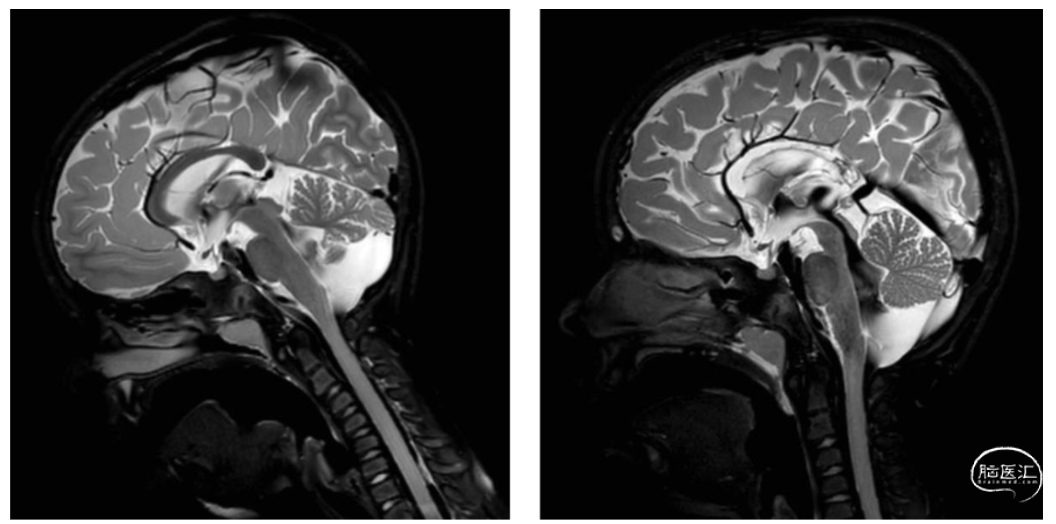

4例患儿术后出现轻微手术并发症。2例发生慢性硬膜下血肿,采用硬膜下腹膜分流术治疗;1例术后共济失调;1例患儿发生短暂胼胝体分离综合征。术后第一年内无患儿死亡,随后2例死亡,其中1例术后2年颅内出血死亡,1例车祸去世。胼胝体切开术后通过高分辨率MRI成像可证实胼胝体手术后改变(图1)。

图1. 胼胝体切开术患儿术前(左)和术后(右)MRI成像。